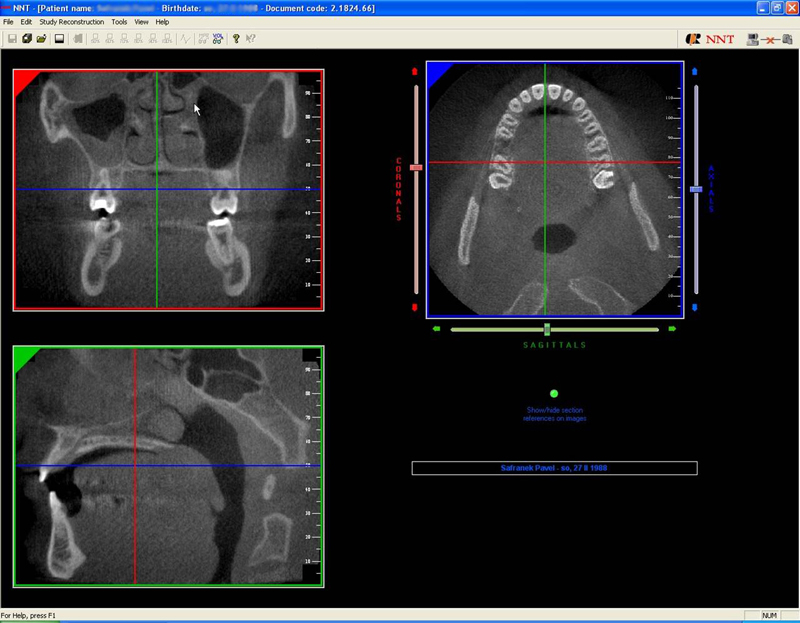

NewTom GiANO

Jedná se o nejnovějším přístroj ze skupiny dentálních hybridních CBCT (3D) + 2D (pan i ceph) systémů. Přístroj umožňuje na základě jediného snímkování vytvořit všechny typy RTG zobrazení, které jsou pro lékaře potřebné.

Používaná technologii tzv. „kuželového paprsku“ a speciální senzory pro minimální zátěž při snímkování pacienta

(o více jak 80% nižší dávka proti klasickému CT).

Pomocí tohoto přístroje je možné zjisti skutečnou situaci v čelistních kostech pacienta tedy množství kosti - můžeme změřit skutečnou šířku i výšku kosti, i kvalitu kosti (hustotu) v místě uvažované implantace. 3D (tříprostorové) zobrazení umožňuje

zvýšit prostorovou představu operatéra ještě před vlastní operací a zároveň pacientovi lépe objasnit a ukázat oblast plánovaného zavedení implantátu.

Pomocí počítačových programů – NewTom Implant Planning a coDiagnostiX si lékař sám provádí veškerá potřebná zobrazení a měření.

Vyšetření pomocí tohoto přístroje a získaná data používáme

pro každou implantaci, dále ve stomatochirurgii (zlomeniny čelistí, zuby moudrosti, cysty, onemocnění čelistního kloubu), ortodoncii (retinované zuby, nadpočetné zuby), parodontologii atd.